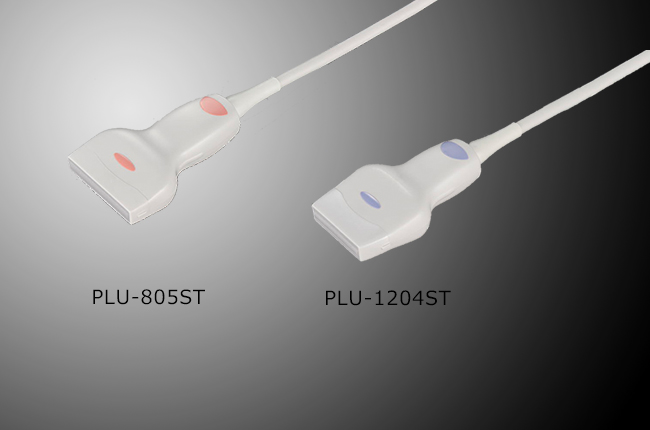

Підтримка широкої лінійки широкополосних мультифокальних датчиків з частотою до 14 MHz.